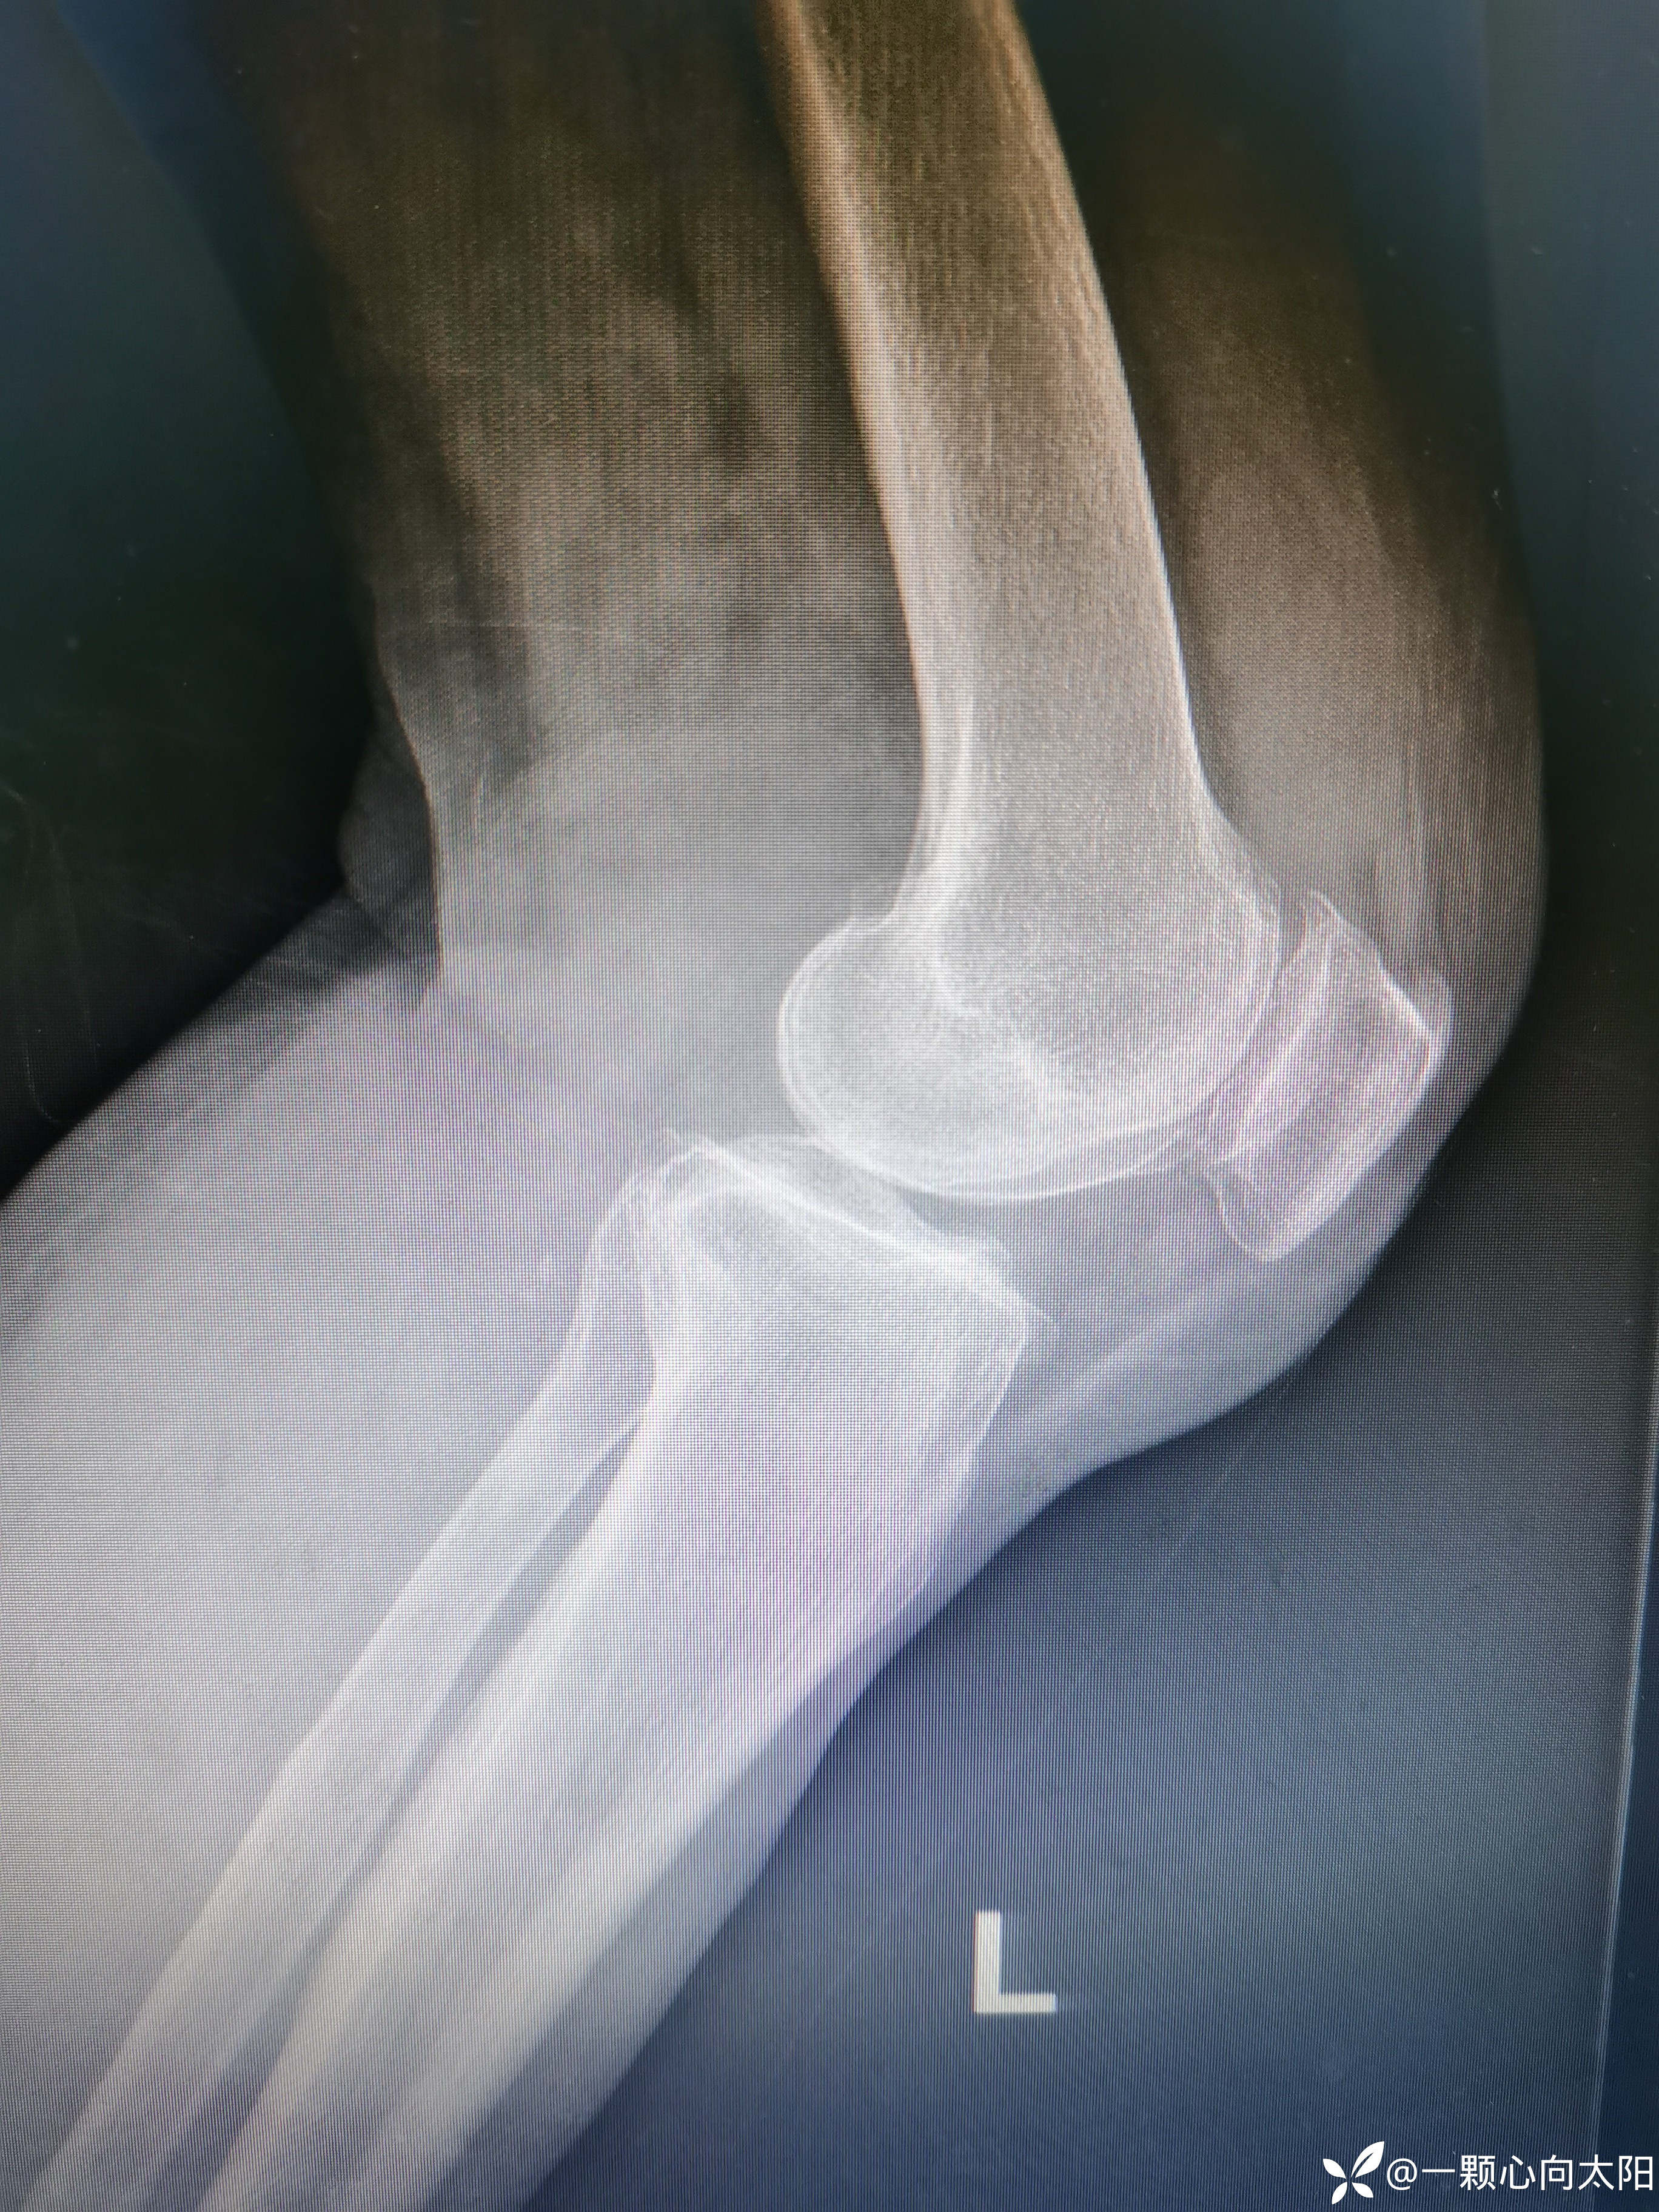

69岁,女性患者,以“外伤致左膝关节疼痛伴活动受限3小时”为主诉入院。